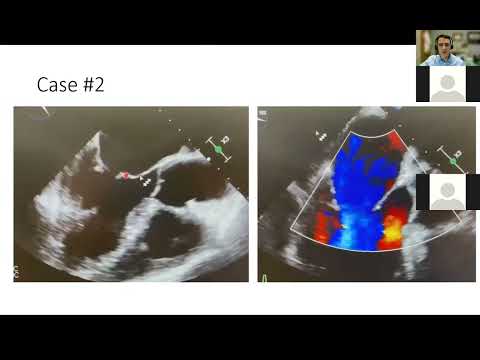

J. Kisslo | Defining Secondary Mitral Regurgitation: Get it Right!